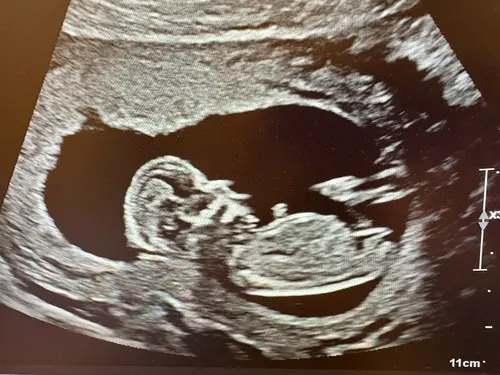

Hi, kunnen jullie zien of het een jongen of meisje is? Hier was ik 13 weken. Ik heb al een meisje en ben heel benieuwd wat dit wordt 馃グ

Ik denk een meisje! Streepje evenwijdig aan de ruggengraat

Meisje inderdaad

Dat is een meisje